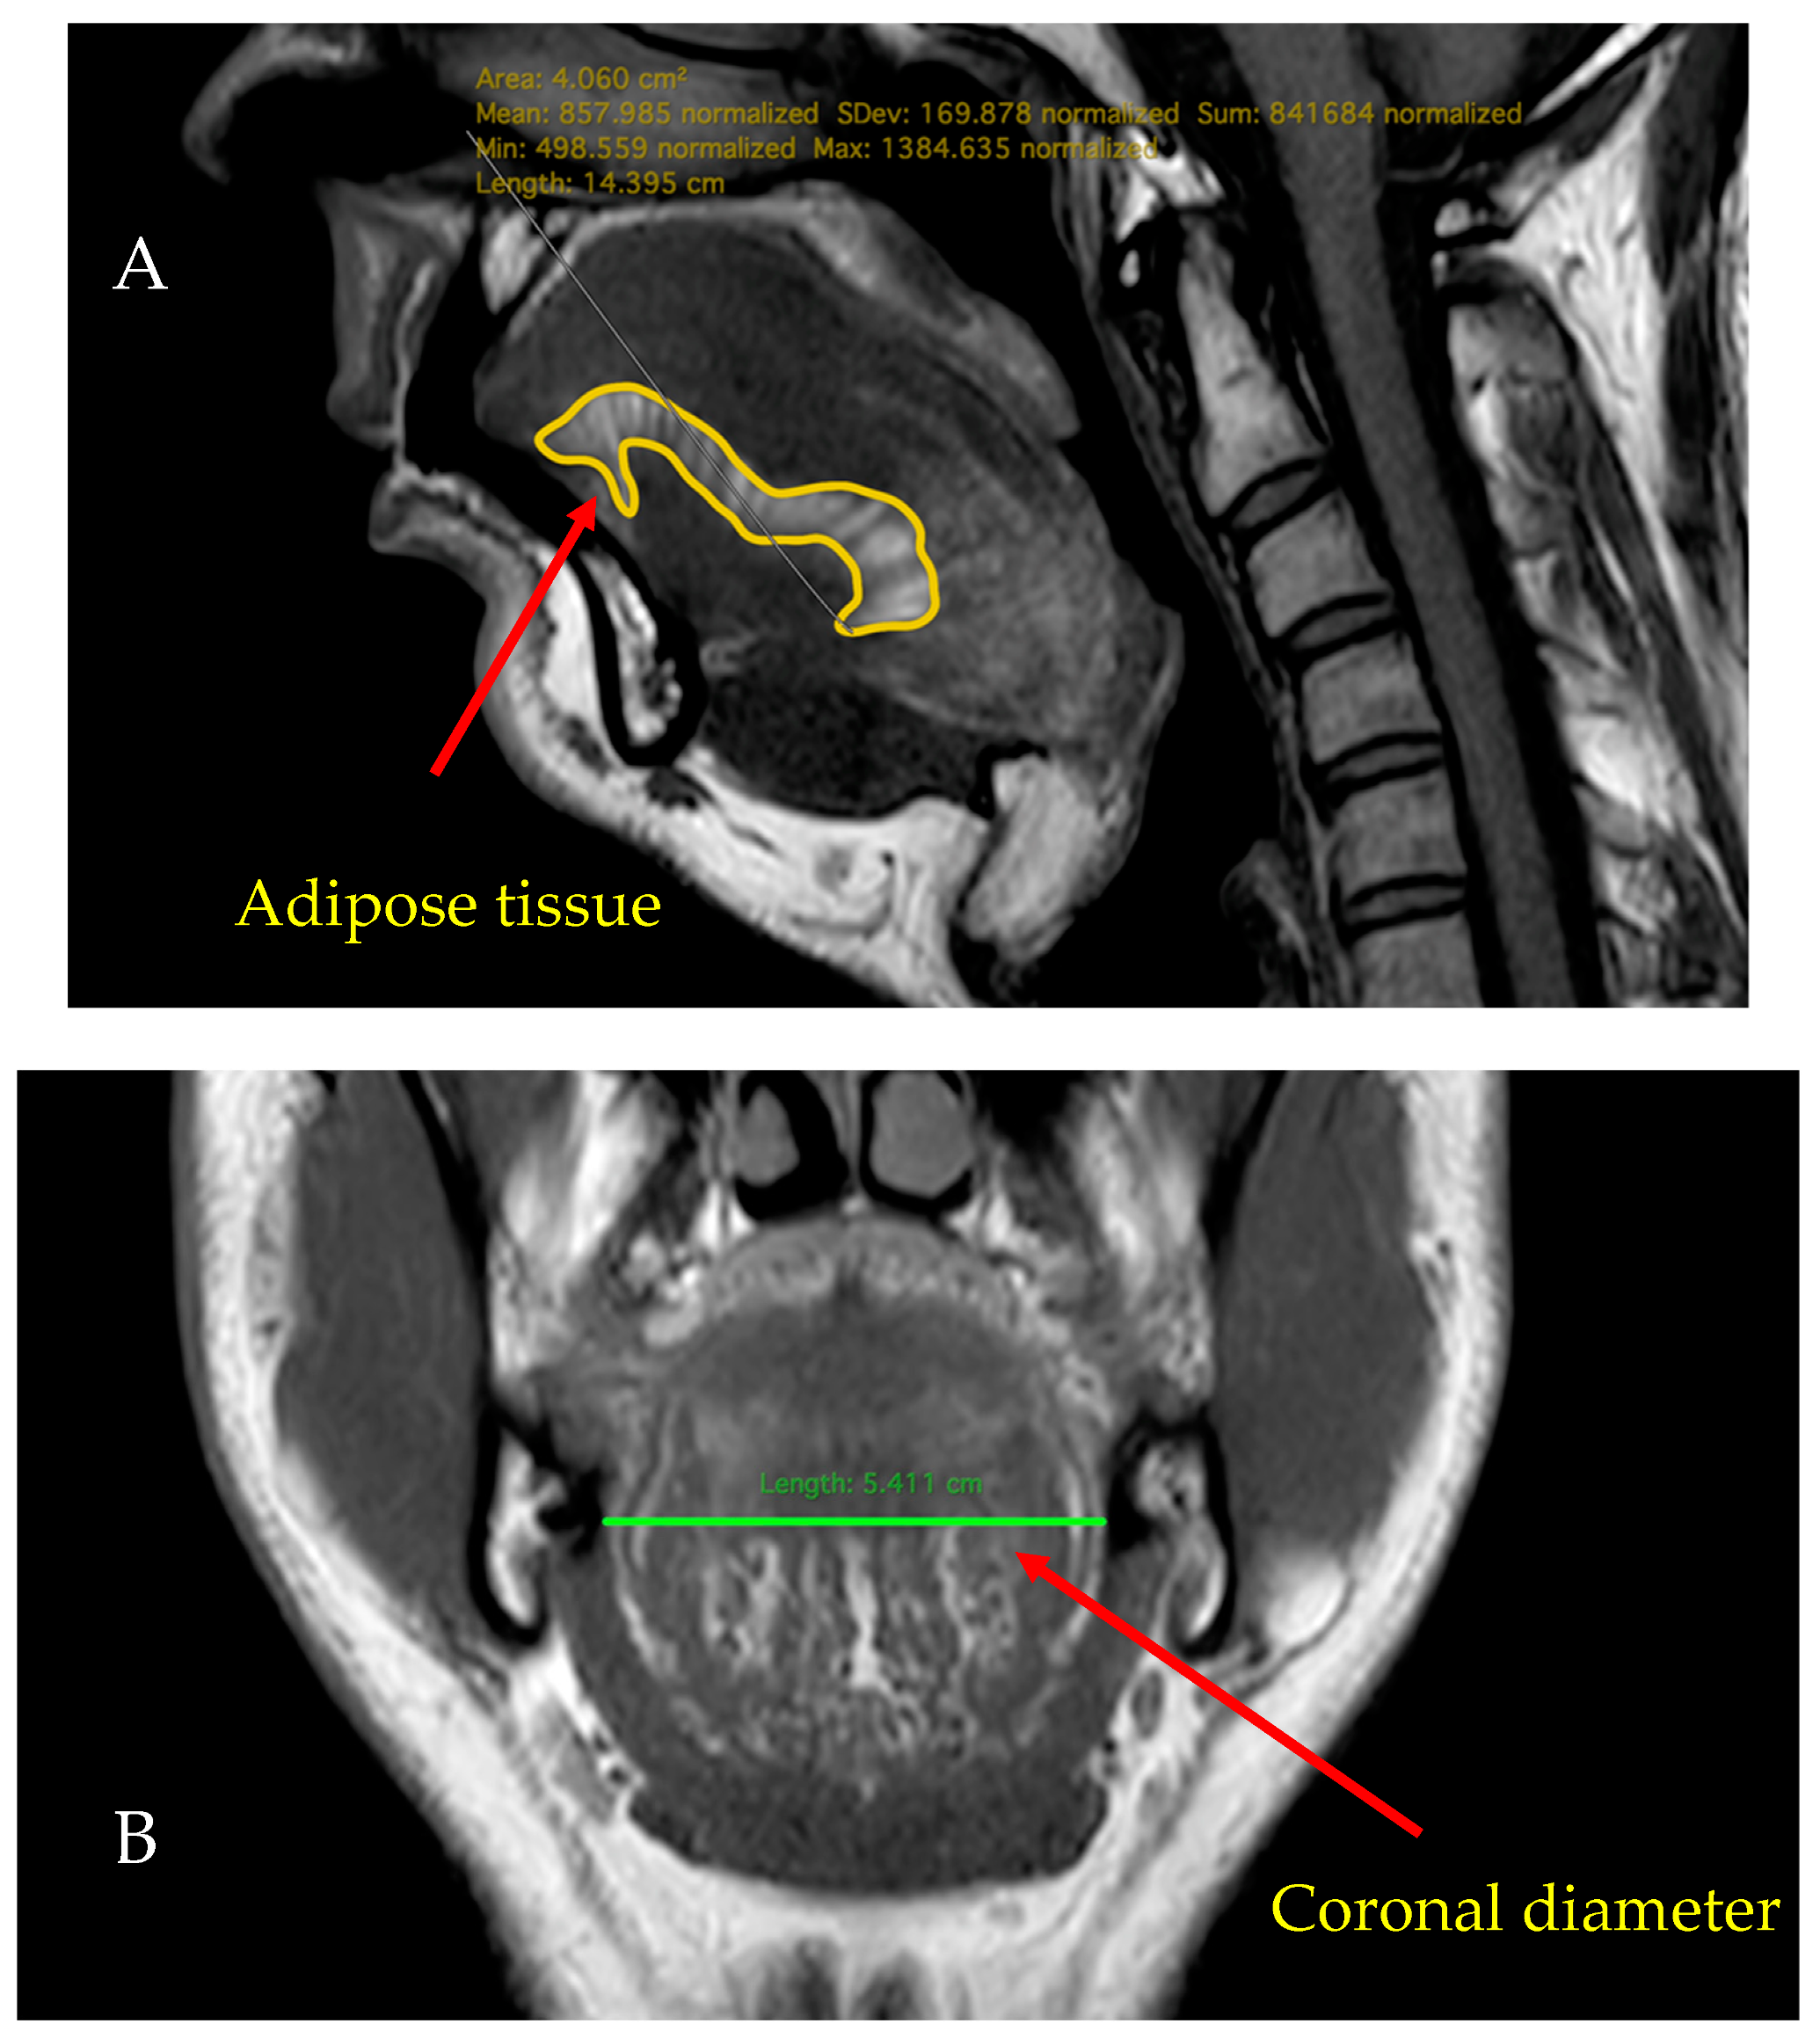

2.4. MRI

| Coronal diameter (cm) | 4.57 ± 0.48 | 4.84 ± 0.45 | 0.006 *** |

| Fat midsagittal (cm2) | 8.45 ± 1.72 | 9.19 ± 1.63 | 0.036 ** |